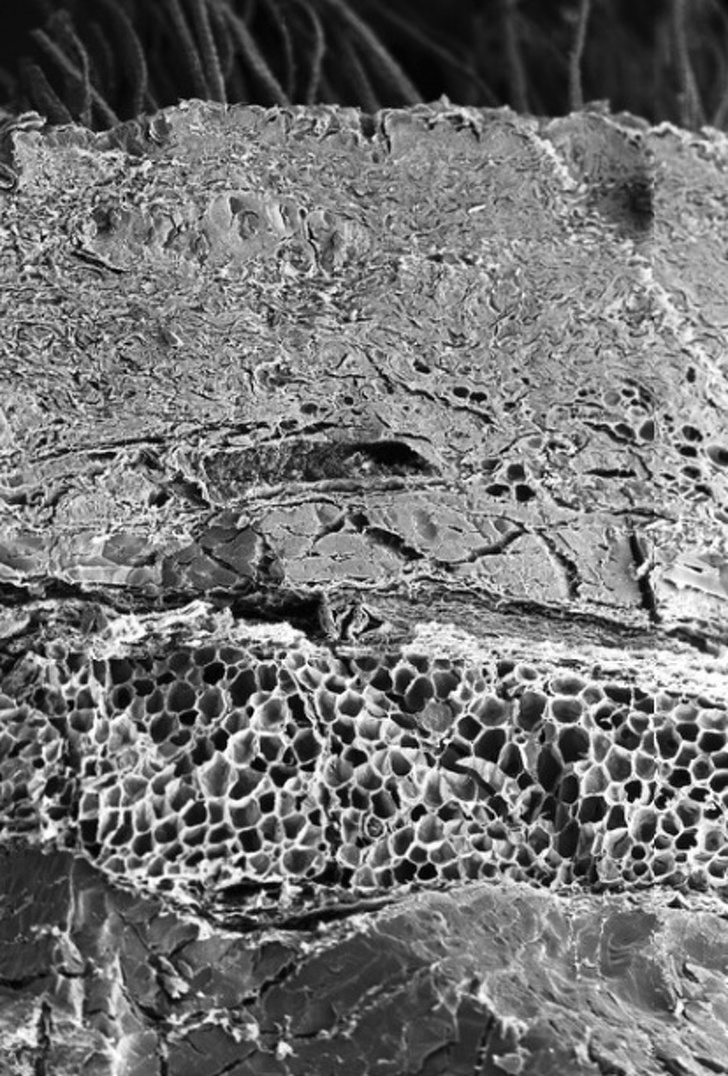

Below are 12 pictures of various organs, processes, and enzymes pertaining to the human body that were captured using a microscope.

#12. Bone